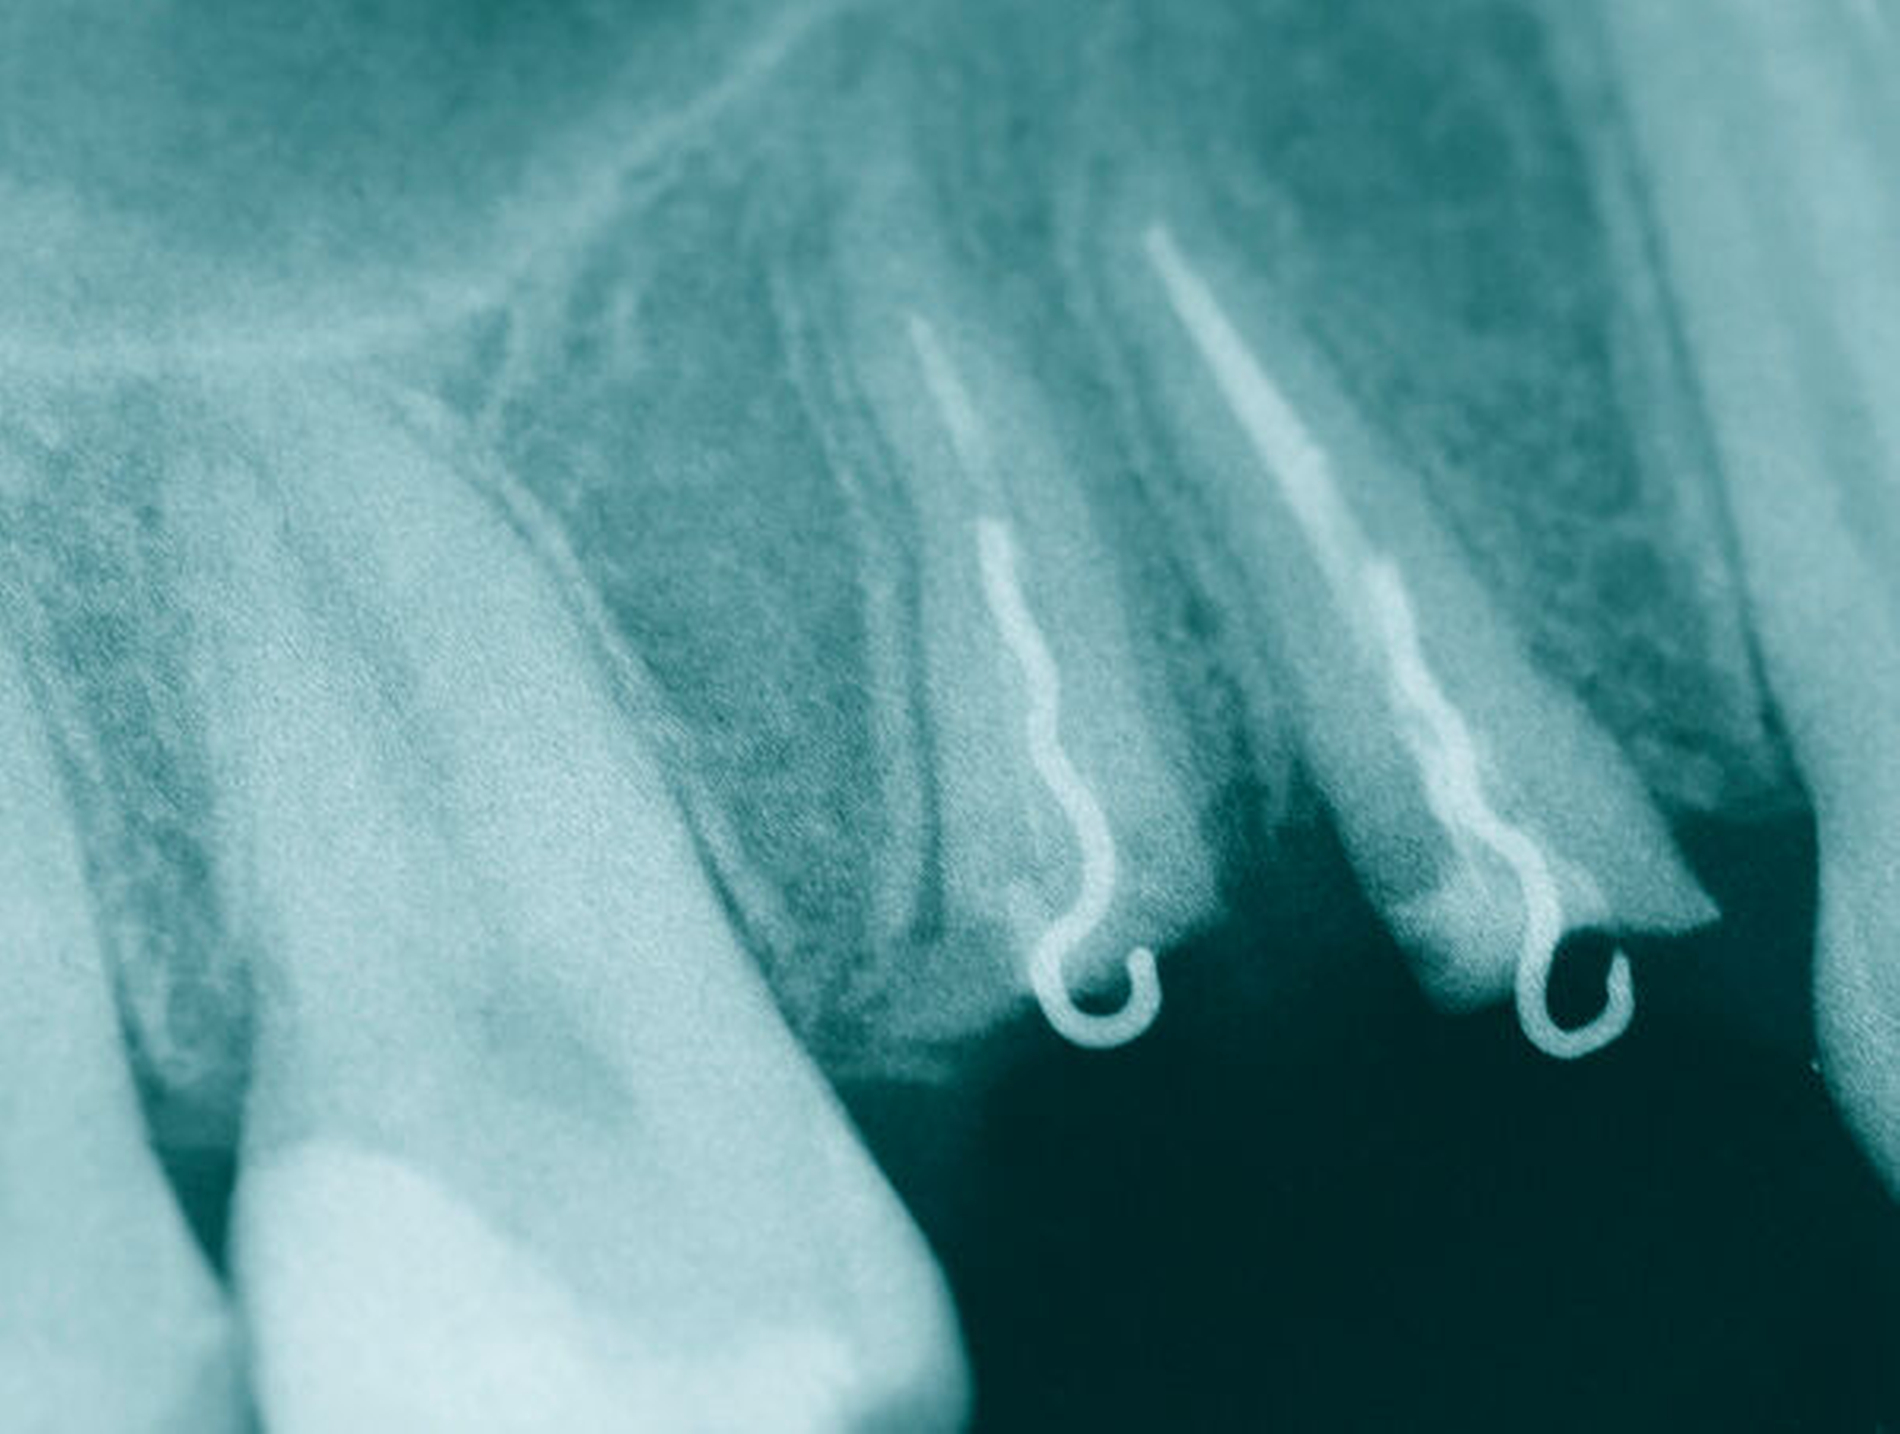

Nach der endodontischen Behandlung der Zähne 14 und 15 erfolgte die chirurgische Entfernung des mobilen vestibulären beziehungsweise oralen Kronenfragments sowie der infragingival frakturierten Wurzelanteile. In der gleichen Sitzung erfolgte die Aufklappung vestibulär und oral, um nach Trocknung der Zahnstümpfe eine adhäsive Befestigung von zuvor auf dem Modell gefertigten Drahtschlaufen (018``Stahl: Dentalline, Deutschland) zu ermöglichen. Diese wurden mittels dual härtendem Composit (Rebilda DC, Voco) intrakanalär verankert. Mithilfe eines weiteren, an den mesialen und distalen Nachbarzähnen adhäsiv angebrachten Drahtes (17x25 TWIST, 3-fach verseilt; Dentalline, Deutschland) und einer elastomeren Kette (Energy Chain, Rocky Mountain Orthodontics, USA) war es nun möglich, die Wurzelreste orthodontisch aus den Alveolen zu extrudieren. Hierzu waren über einen längeren Zeitraum mehrere Behandlungstermine nötig, bei denen die Gummizüge entsprechend des Behandlungsfortschritts gewechselt wurden. Des Weiteren erfolgten in regelmäßigen Abständen Inzisionen im PA-Spalt, um eine Mitwanderung des Knochens zu vermeiden. Anders als bei festsitzenden Multibandapparaturen ist eine definitive Kraftangabe bezüglich der Extrusion nicht möglich, da sich die Kräfte mit fortschreitendem Extrusionsgrad und je nach verwendeter elastomerer Kette ändern.

Auf eine provisorische Versorgung zur Kaschierung der fehlenden Zahnkronen musste in der Zeit verzichtet werden. Dies wurde von der Patientin akzeptiert. Gleichwohl war die Patientin sehr froh, als nach zehn Monaten die Wurzeln mit 4 mm so weit nach crestal extrudiert schienen, dass nach einer anschließenden viermonatigen Retentionsphase die provisorische Versorgung erfolgen konnte. Zwischenzeitlich wurde Zahn 15 revidiert, da die endodontische Versorgung initial, aufgrund der Fragmente und somit ungenauer endometrischer Längenbestimmung, nicht exakt genug erfolgen konnte und die Vorraussetzungen vor der weiteren Versorgung möglichst optimiert werden sollten. Anschließend wurden beide Zähne mit adhäsiven Stiften (Komet) und Aufbaufüllungen (Optibond FL, (Kerr); Rebilda DC, (Voco)) versorgt und für die Aufnahme der LZPV-Kronen präpariert. Es erfolgte eine langzeitprovisorische Versorgung mit verblockten, laborgefertigten Kunststoff Provisorien (Dentallabor Wehner, Ludwigshafen).